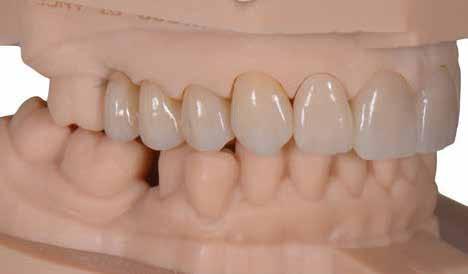

Teljes ívű rehabilitáció primer vázra ragasztott lítium-diszilikát szekunder koronákkal

A tesztprojektünk megerősítette, hogy a KATANA Zirconia

potenciállal rendelkezik, és az indikációs területe határtalan.

pozicionálása a virtuális nyersdarabban, marás után pedig az illeszkedés

Zirconia YML kiváló minőségű anyag, amely nagy esztétikai határtalan. Meglepően egyszerű a restaurációk tervezése és pedig a felületek simák, a szélek élesek és határozottak, pedig pontos.

Amikor a fogászati cirkónium rendkívül esztétikus anyaggá fejlődött alkalmassá válva a monolitikus kialakítású vagy minimális labiális visszavágású pótlások készítésére, a kézzel végzett munka (kerámia rétegezés) mennyisége csökkent. Ugyanakkor minden fogtechnikai laboratóriumnak több elérhető nyersdarabra volt szüksége, és az indikáció-specifikus anyag -

választás igénye bonyolította a tervezési folyamatokat.

Egyes fogtechnikusok előszeretettel játszanak a különböző korongokkal és az automatizált és kézi munkafolyamatok kombinációjával, hogy pontosan megfeleljenek a páciens és az indikáció-specifikus igényeknek. Mások azonban egy gyorsabb és szabványosabb utat választanának